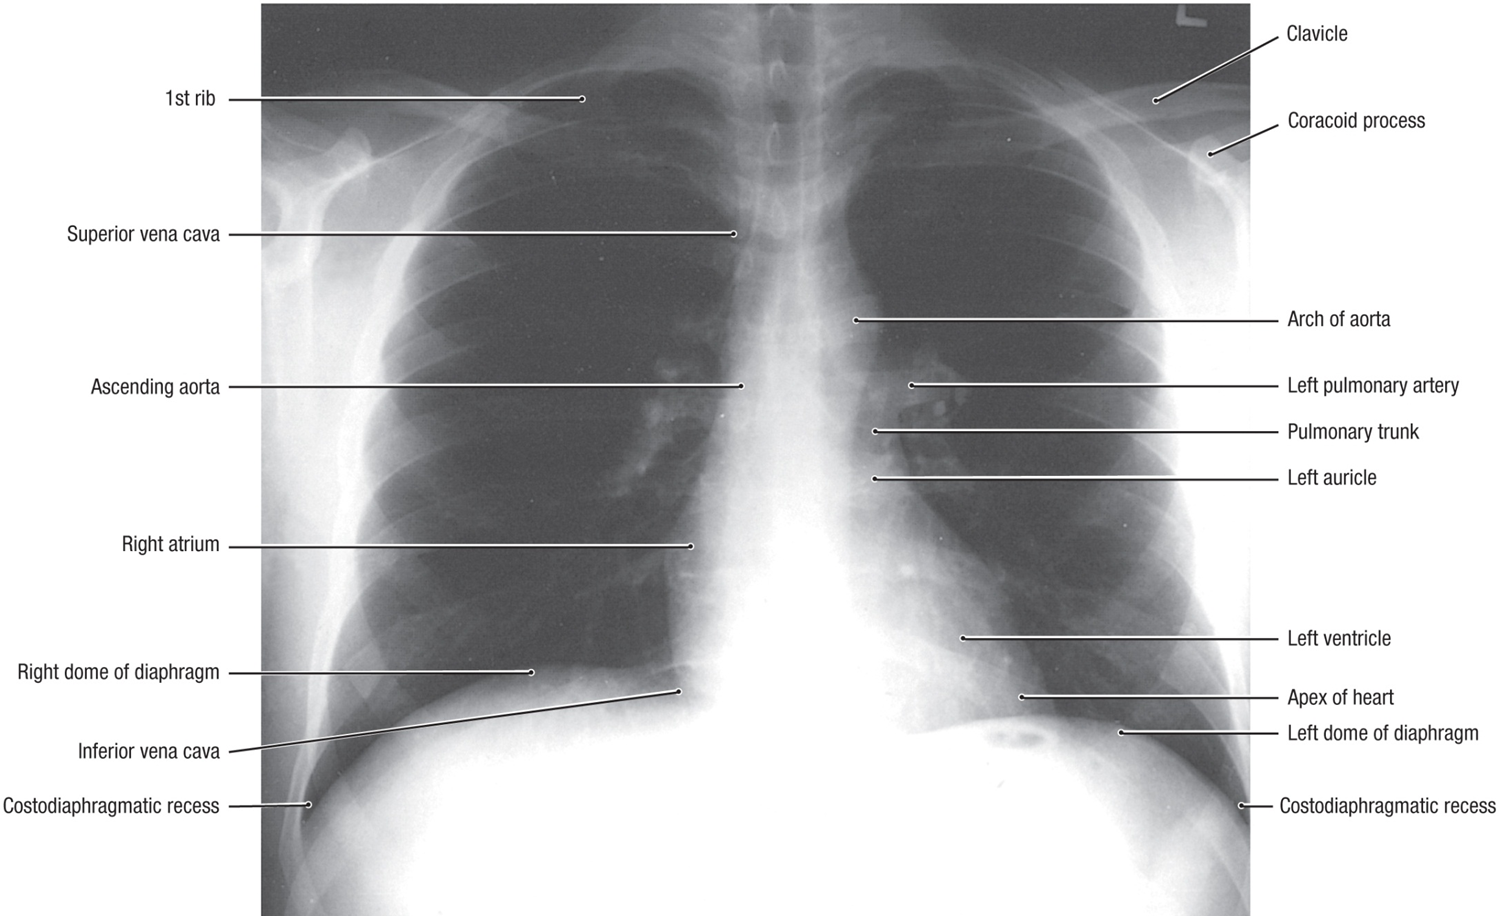

chest x-ray